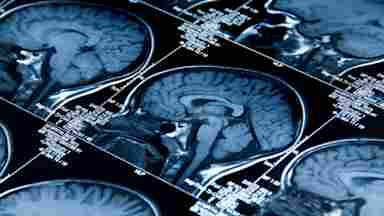

Figure 1 shows that the combined effect of both marijuana and nicotine was associated with the smallest hippocampal volume among participants.